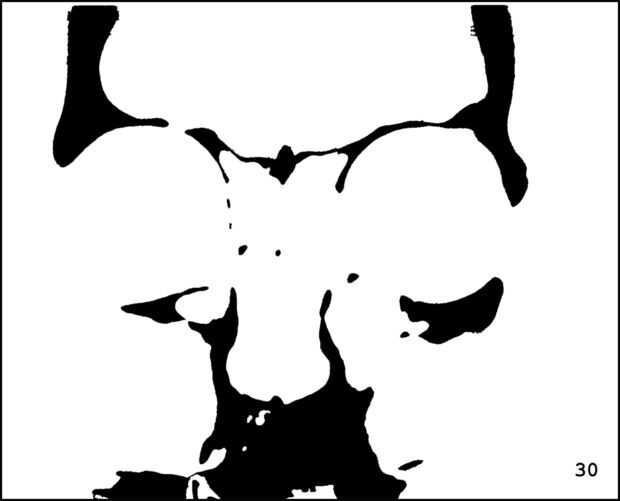

¡ Wow! Este fue por menos de 12 horas y tengo 1.000 visitas! Esto es sólo mi segundo instructable, así que estoy encantada. Decidí seguir adelante y publicar las imágenes que utiliza. Se trata de MRI de mi esposa, así que ella sólo puede tener lo mundos primer código abierto jefe. Mi lámpara utiliza solamente las primeras 16 capas, pero te di todos 34 que representa. Seguir adelante y usar estas imágenes, pero si lo haces, por favor me manden una imagen de lo que te ocurrió así que puedo hacerla sentir un poco famoso. ¡Que te diviertas!